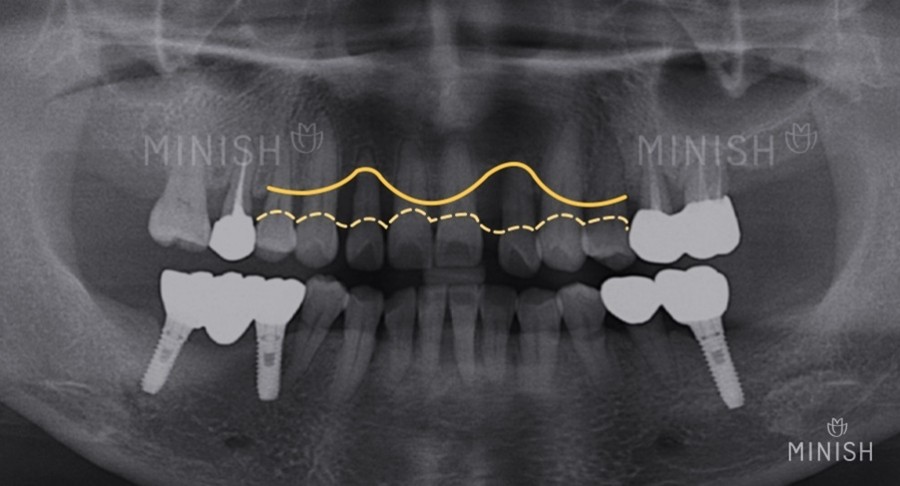

잇몸뼈가 심하게 소실된 경우

크라운 브릿지의 인접치아 손상 정도